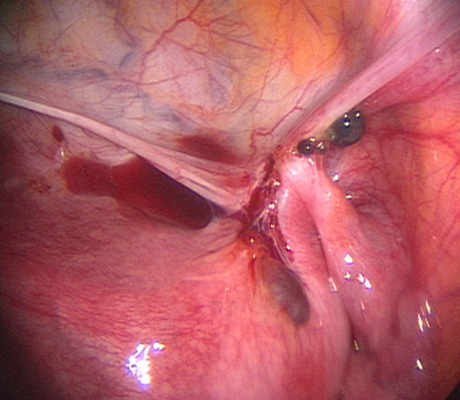

Endometriosis is a non-cancerous condition where the endometrial tissue or womb lining which normally grows only in the uterus is found in other parts of your pelvis, for example the ovaries, fallopian tubes, rectum, bladder, appendix and pelvic walls. This womb lining that grows outside the uterus responds also to hormones but at the time of your periods it can not be expelled (as the womb lining) and causes pain, cysts in the ovaries (called chocolate cysts), inflammation in your pelvis, scar tissue, pain with sexual intercourse, chronic pelvic pain, pain when passing bowel motions, lower backache, symptoms similar to urinary tract infections, premenstrual discomfort, etc.

Laparoscopy is an operation (keyhole surgery) conducted under general anaesthesia. A telescope is introduced into a small incision in your navel, other small incisions are made for using special laparoscopic instruments and all the pelvic organs are examined with magnification (Video-laparoscopy) ; then the endometriosis is treated. Video Laparoscopy allows conservative surgery (hysterectomy is NOT the usual treatment for endometriosis) which means laparoscopic excision of the endometriotic implants, with restoration of the normal anatomy and preservation of the uterus, tubes and ovaries.